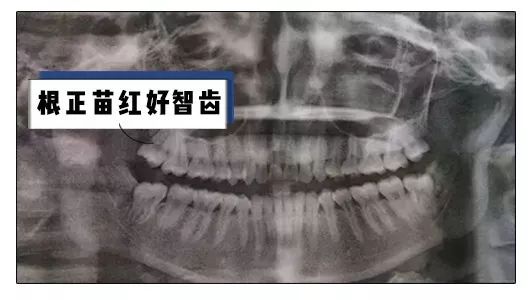

什么样的智齿不需要拔呢

那就是这样子的